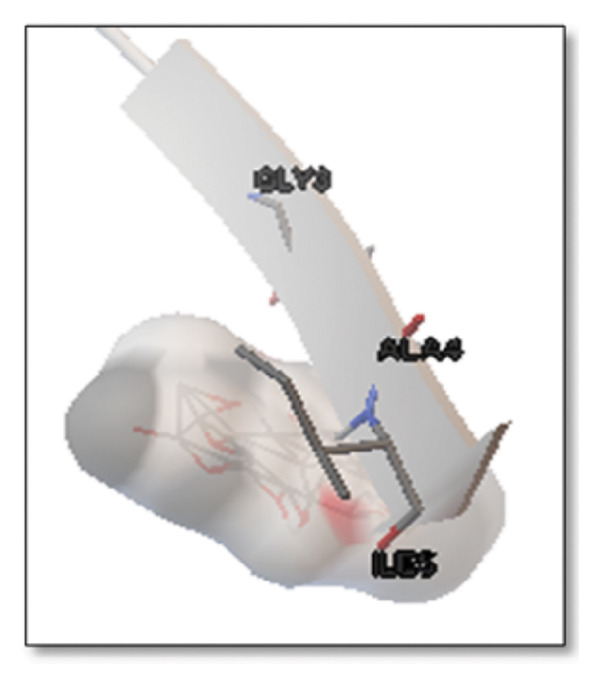

Against the core Aβ peptide, ginkgolide again showed the lowest binding energy (−8.40 kcal/mol), though no direct hydrogen bond interactions were detected in the lowest‐energy pose. Ginsenosides (−4.36 kcal/mol) demonstrated stable interactions, notably forming H‐bonds with ALA4 and LYS2.

Ginsenosides (−4.36 kcal/mol) formed a highly optimal bond with ALA4 (carbonyl oxygen [O] donor) with a short distance (2.56 Ǻ) and a near line angle (160.82°). Cyanidin (−3.94 kcal/mol) also formed H‐bonds with ILE5 and ASN1. The reference drug memantine exhibited significant binding at −3.56 kcal/mol, forming an H‐bond with the critical amyloidogenic residue ILE5 D‐A 2.80 Ǻ, angle: 159.52°. Figure 4 summarizes the binding characteristics for Aβ peptide.

Similarly, interactions with the clusterin receptor (also known as ApoJ) were mediated through a crucial binding site involving PHE240. PHE240 is a key hydrophobic residue within clusterin’s large chaperone domain. Our findings suggest that ginsenosides use a hydrophobic interaction at this specific residue to modulate the chaperone activity, thereby potentially stabilizing clusterin in a conformation that effectively prevents $\text{A}\beta$ from forming toxic oligomers [ref. 46]. Aβ peptide ginsenosides were shown to interact directly with ALA4 and LYS2. These particular residues are located in a critical hydrophobic region of the Aβ peptide, which is essential for its initial self‐association and subsequent aggregation into neurotoxic oligomers and fibrils. The ginsenoside interaction at these sites provides a compelling direct mechanism for how these compounds could inhibit Aβ aggregation, a central pathological event in AD [ref. 47].